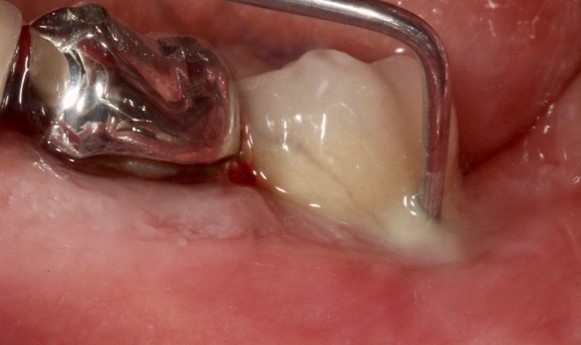

Au stade de « péri-implantite » il s’agit d’une atteinte inflammatoire des tissus mous entourant un implant. Le diagnostic clinique comprend un saignement au sondage, avec une suppuration quasi systématique, et une profondeur de poche péri-implantaire supérieure ou égale à 5 mm. Radiographiquement, un aspect radioclair de déminéralisation osseuse marginale supérieure ou égale à 2 mm entoure une partie plus ou moins étendue du corps de l’implant (fig 1 et 2).

Figure 1: suppuration au sondage d’une molaire atteinte de péri-implantite